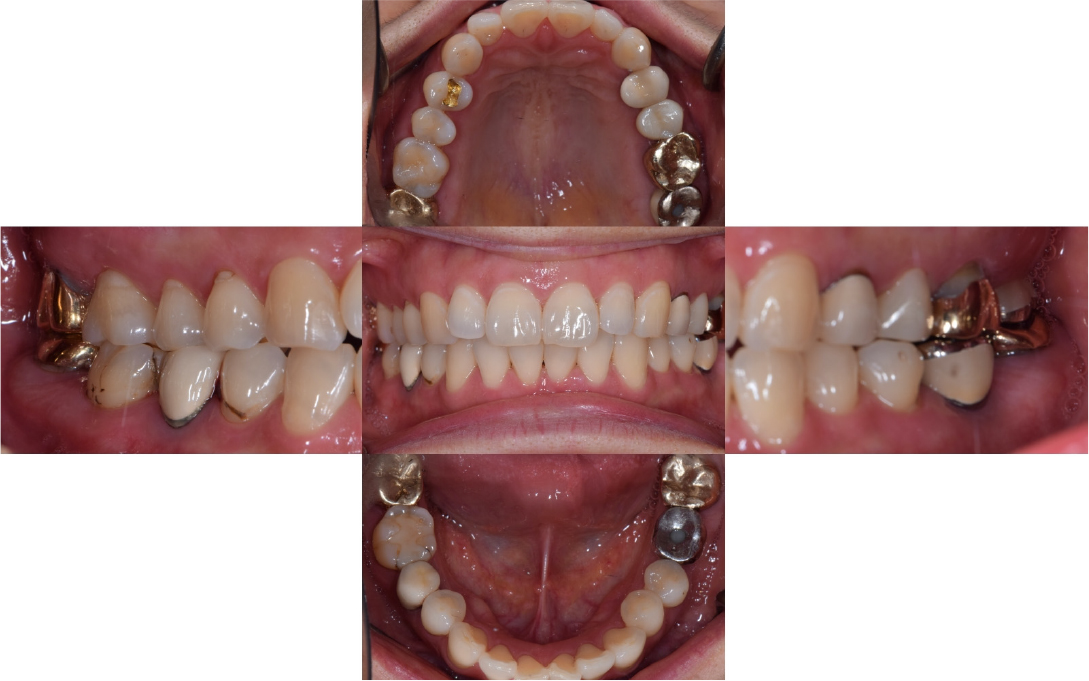

After 4 months of the first surgery, the ISQ value was 71, showing favorable stability, the prosthesis was placed consecutively, and healing progress was observed (Fig. 8A, 8B). After 5 months, the final prosthesis was completed (Fig. 9A, 9B). Supported treatment was initiated and radiographs were taken after 6 months (Figs. 10, 11, 12). In the radiograph analysis, the alveolar bone surrounding the dental implant was stable, with ossified bone verified. In a 6-month interval, the supported treatment was conducted in April 2022, showing no signs of peri-implant gingivitis or bone resorption (Figs. 13 and 14).